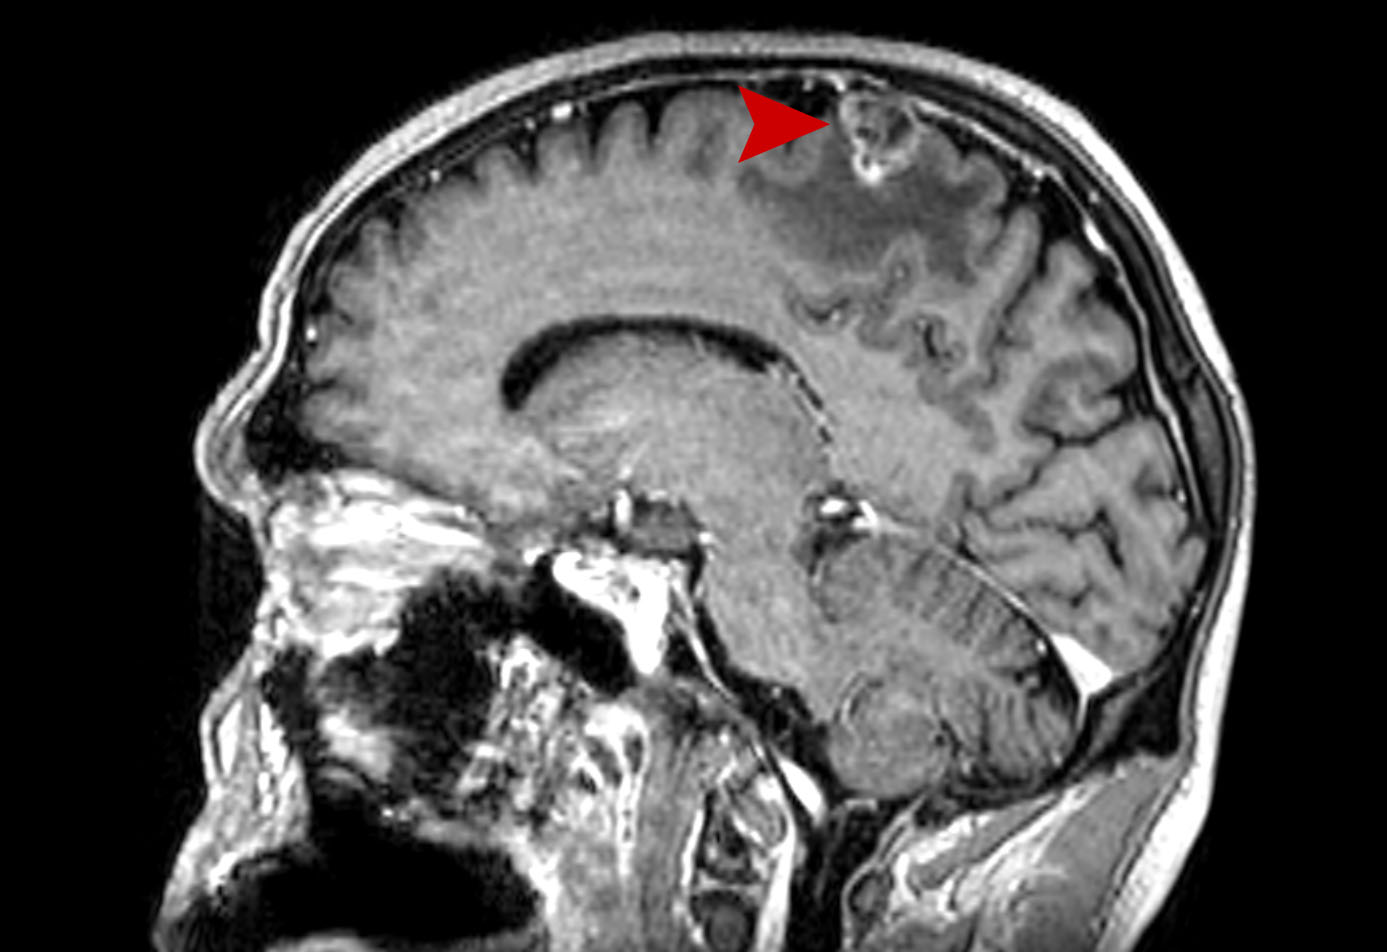

Μηνιγγίωμα Grade II Θεραπεία με CyberKnife #13

Θήλυ 54 ετών με ευμεγέθη υποτροπή χειρουργηθέντος Grade II μηνιγγιώματος δεξιά κροταφικά. Σύγκριση MRI 2/2019…